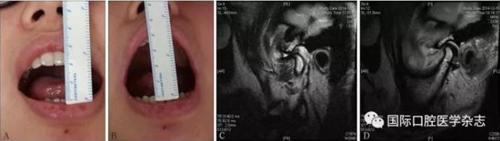

A:術前開口度;B:術后開口度;C:術前影像學檢查片;D:術后影像學檢查片。

圖 18 關節(jié)盤復位錨固術前后對比